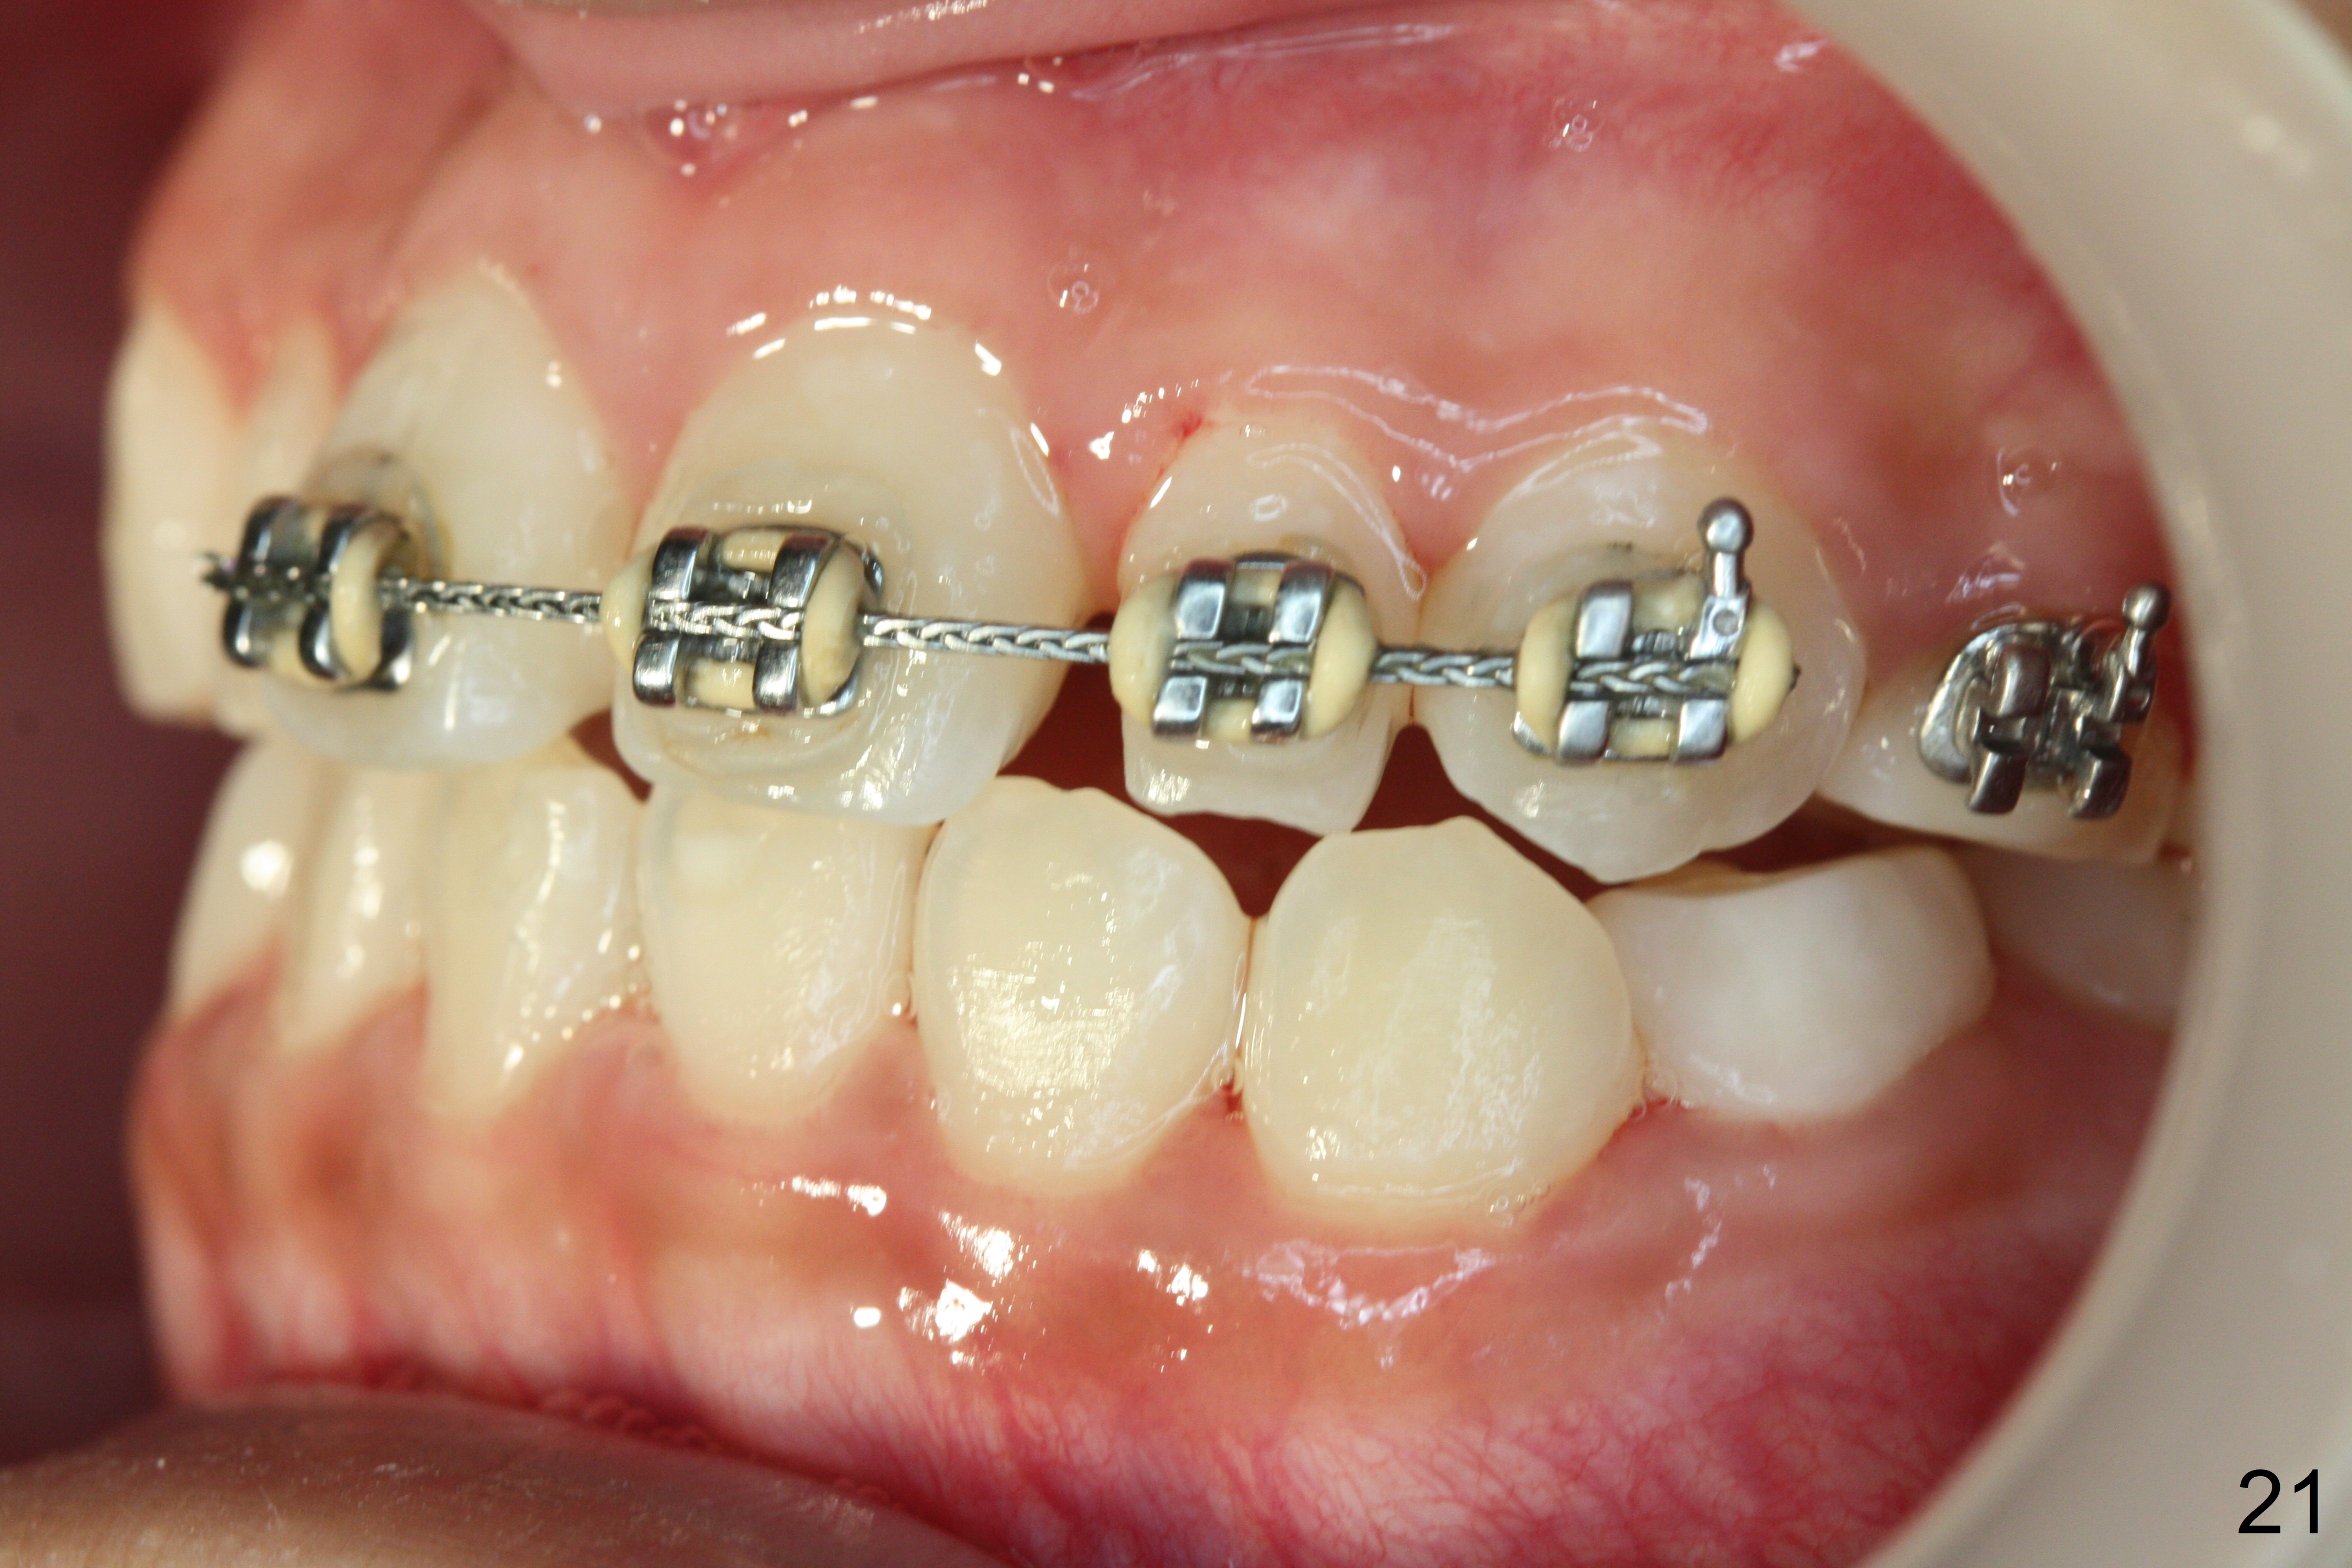

OK Xin, just evaluated the case. If she started with the anterior dental crossbite and you are barely over-corrected right now, I would be very comfortable discontinuing treatment. At her age, there is nothing that can no longer be dealt with beautifully when it is more age appropriate.When anterior cross bite is corrected 19 months post banding, the tooth #10 (microdontia) has tendency of edge-to-edge (Fig.16,17). Power chains are used to create space for #11 to erupt fully before bracketing. In spite of the effort, the peg lateral remains edge-to-edge 23 months post banding (Fig.18,19). The segmental 19x26 braided wire retains as a retainer to prevent #10 from cross bite. The facial profile is more or less normal immediately post debracketing (Fig.20). The anterior occlusion appears to remain basically the same 7 months post debracketing (Fig.21,22). UR3 erupts, while the diastema mesial to UL2 enlarges so that the arch wire appears shorter. UL2,3 appear to be in cross bite 14 months post debracketing, while Es retain at the age of 13 (delayed development, Fig.23).